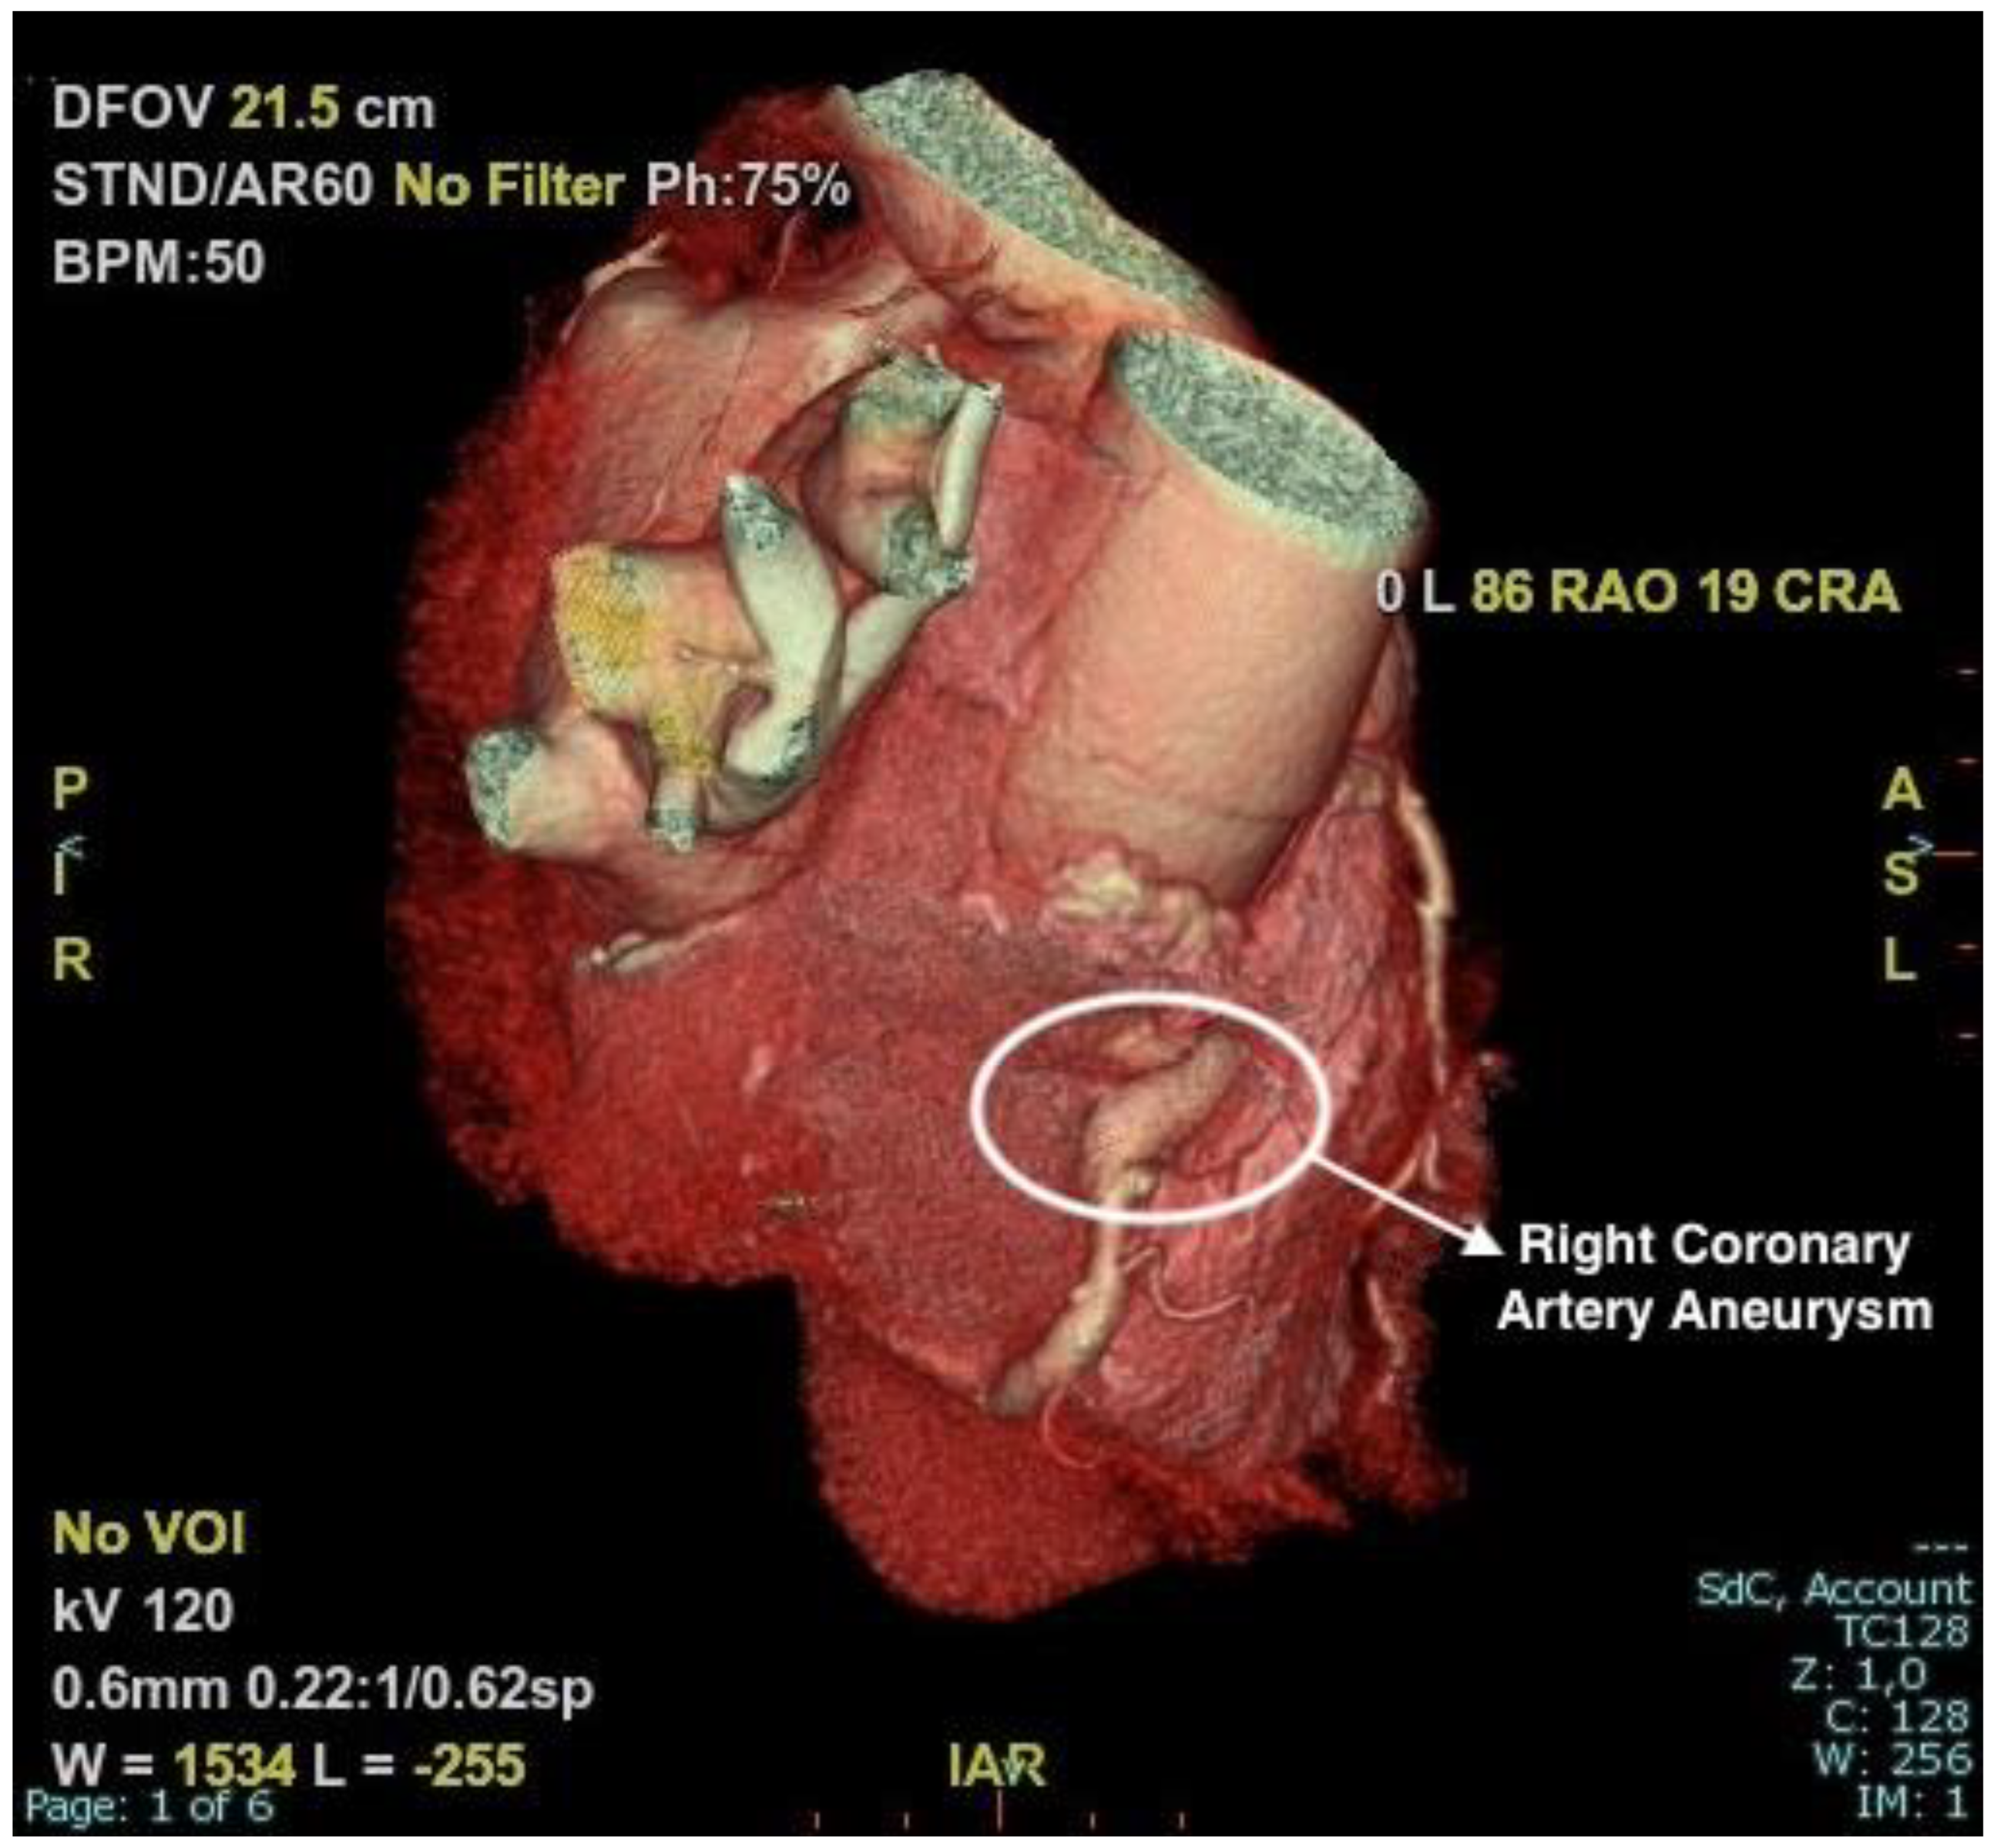

2.2. Examinations

2.3. Management